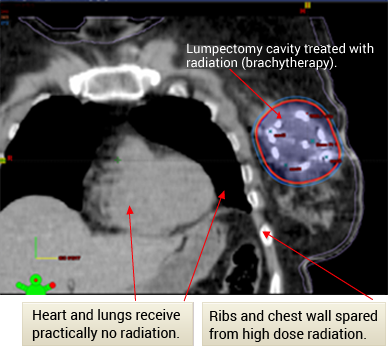

Prior to radiosurgery: painful focus of breast cancer in the right hip with erosion of pelvic bone.

Radiosurgery plan targeting the pelvic tumor and sparing the pelvic organs.

After completion of radiosurgery: complete resolution of pain and the focus of breast cancer in the right hip, with interval healing of pelvic bone (green arrow). Brown arrow points to normal bladder and pelvic organs.